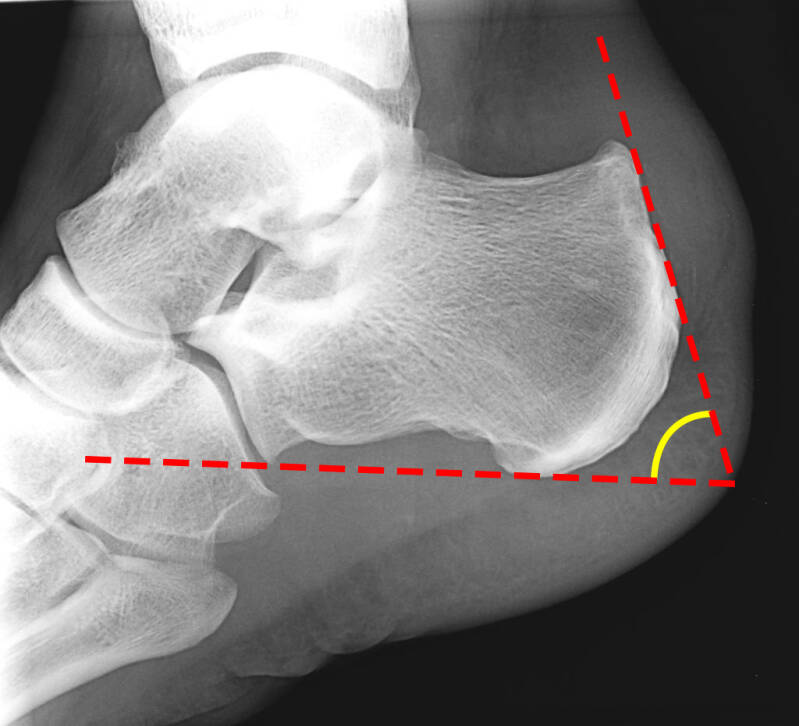

- Radiografia: indispensabile per identificare alterazioni del calcagno ed eventuali calcificazioni nel contesto del tendine d’Achille;